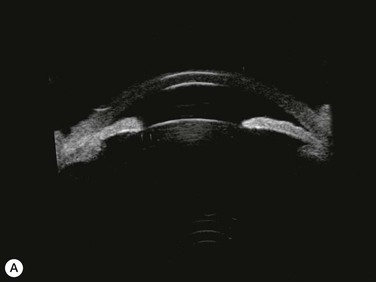

Substantial increases in anterior chamber depth and angle width following cataract extraction with intraocular lens (IOL) implantation have been demonstrated in eyes with PAC (Fig. 108-2A,B).23–25 The narrower the preoperative anterior chamber angle, the greater the alteration of angle configuration. Whereas iridolenticular contact was observed in a phakic eye, there was no iris and IOL contact in a pseudophakic one (Fig. 108-2A,B). The iris plane shifted backward, deepening the central anterior chamber by approximately 850 µm. Preoperative biometry performed in a series of 52 eyes of 48 consecutive Thai middle-aged patients who had developed acute PAC within 6 months showed that average natural lens thickness and central anterior chamber depth were 4.83 mm and 1.8 mm, respectively.26 Since the IOL (PMMA, silicone, acrylic) thickness in the 20–25 D power ranges from 0.75 mm to 1.42 mm. Replacement of the natural lens with the IOL provided up to 4 mm more axial distance within the anterior segment eliminating angle crowding and appositional closure. In addition, anterior chamber deepening with a viscoelastic during IOL implantation might break recent PAS.

Several studies have shown that extracapsular cataract extraction (ECCE) with IOL implantation is effective in opening the angle and controlling IOP in refractory PAC.27–30 Currently, ECCE has been replaced by phacoemulsification which offers a higher surgical success rate, less postoperative inflammation and fewer complications. In addition, the clear corneal approach spares the superior conjunctiva for possible filtering surgery, if needed. Phacoemulsification and IOL implantation has been reported to be highly effective in patients with uncontrolled PAC.31,32 However, up to 32% of the patients still had persistent PAS and required long-term treatment with glaucoma medication following lens removal either by ECCE or phacoemulsification and IOL implantation alone (Fig. 108-2A).5,32 Goniosynechialysis is the next step to eliminate the remaining synechiae and control the IOP (Fig. 108-2C).

Patients are treated with antiglaucoma medications and frequent topical steroids. When the inflammation subsides, the medications are then slowly tapered off within a month. Occasionally, a release of aqueous through the paracenteses at the slit lamp may be performed if a high IOP rise occurs. Gonioscopy typically reveals opening of the angle structures with irregular pigmentation on the newly exposed trabecular meshwork and the angle wall (Fig. 108-6). Angle recession or a cyclodialysis cleft are undesirable findings. If successful, anterior segment optical coherence tomography or ultrasound biomicroscopy should demonstrate separation of the PAS and reopening more than half of the entire angle (Figs 108-2, 108-7).